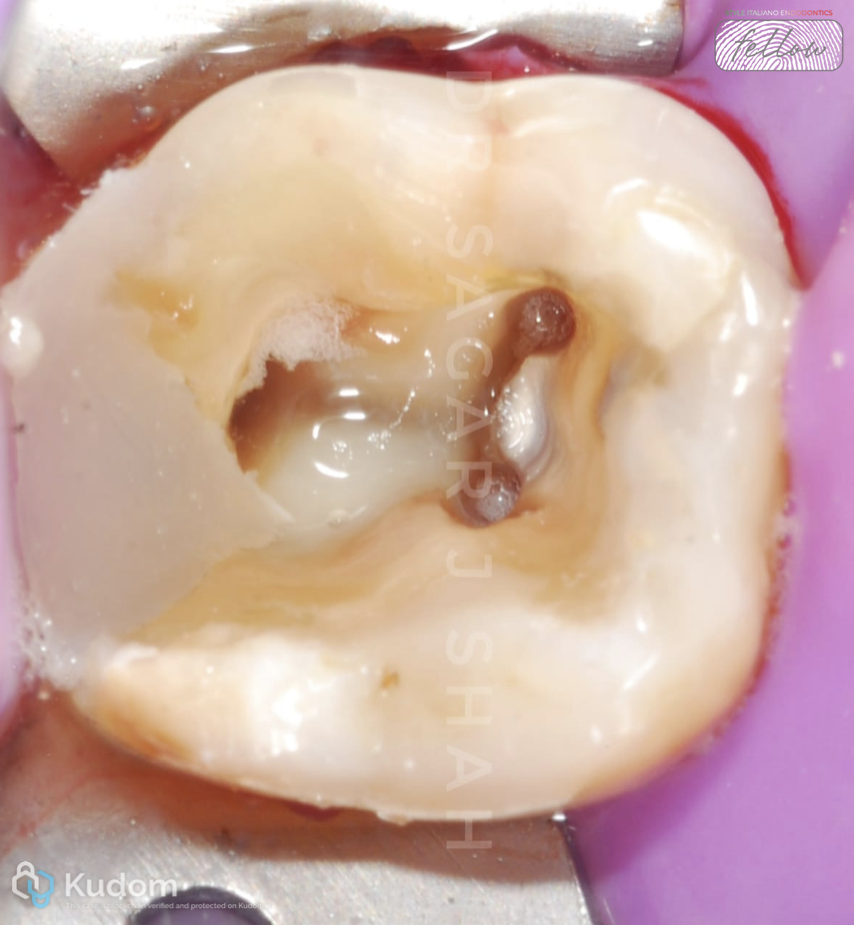

- ANESTHESIA AND RUBBER DAM APPLICATION

- ACCESS OPENING:

- Performed using SF 12, followed by safe end (EX-24) to achieve complete deroofing.

- Ultrasonic used to refine the access.

Fig. 5